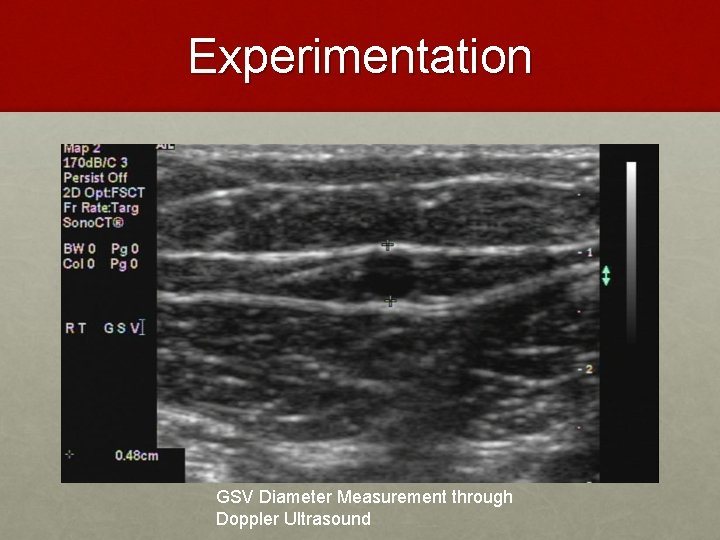

Experimentation GSV Diameter Measurement through Doppler Ultrasound